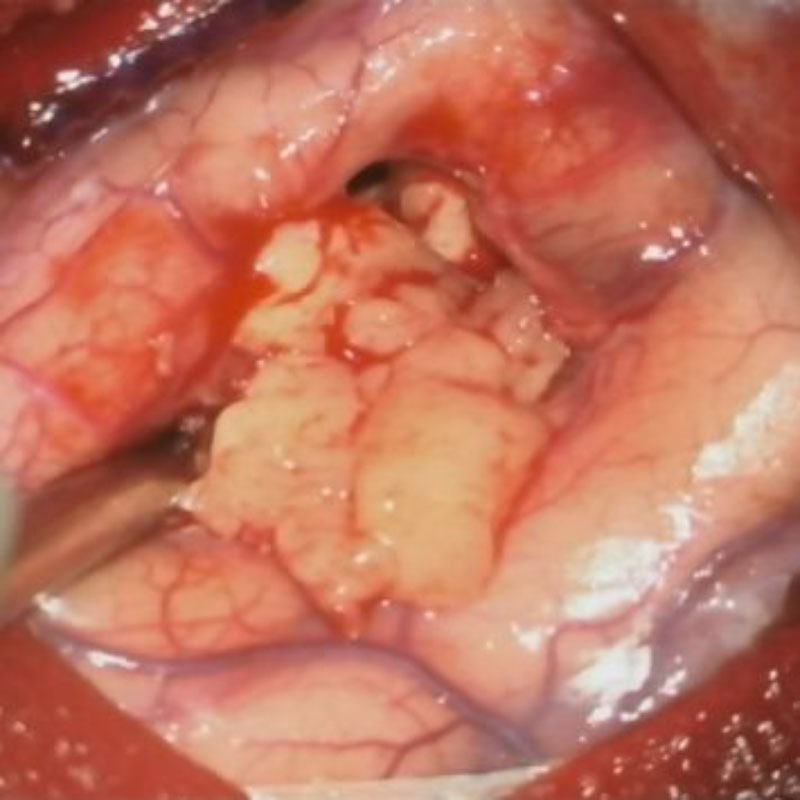

No.’25_107 摘出 前

No.’25_107  摘出 中